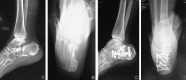

Methods: From October 2012 to December 2013, 23 elderly patients suffering from calcaneal fracture (Sanders II-III) were treated and followed up. There were 15 males and 8 females with the mean age of 68.5 years (range: 65-79 years). According to Sander's classification, 16 cases (16 feet) were type II fractures and 7 cases (7 feet) were type III fractures. Anteroposterior, lateral and axial views of X-ray were taken to detect the calcaneum. CT scan was done to assess the amount of comminution and articular depression. Radiological assessment was performed using Bohler's angle and Gissane's angle. Functional outcome was assessed using the Maryland foot score.

Results: All the patients were followed up for 13.7 months on average (10-20 months). The mean time of bone union was 3.2 months (3-4 months). The mean time of complete weight bearing was 3.2 months (3.1-4.0 months). The soft tissue necrosis was found in 1 case. The mean Bohler's angle and Gissane's angle were 25.31° and 117.5°respectively. The overall excellent to good rate was 82.6%.

Conclusion: Open reduction and internal fixation with locking calcaneal plate can obtain good functional outcome for Sanders II-III calcaneal fractures in elderly patients.